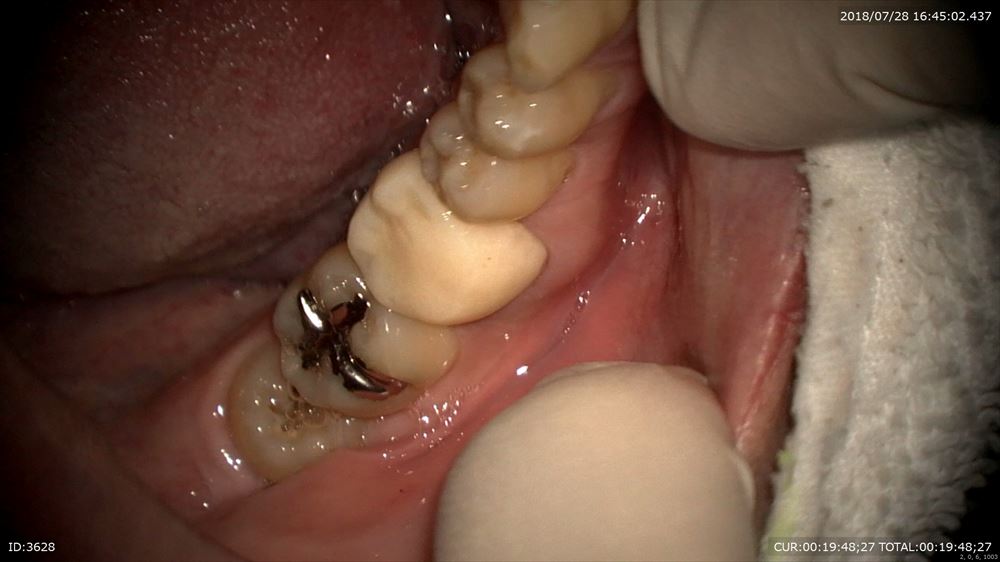

これは別の方

やる事は同じ。ブリッジであってもやる仕事はいつも同じ

仮歯を外してセット